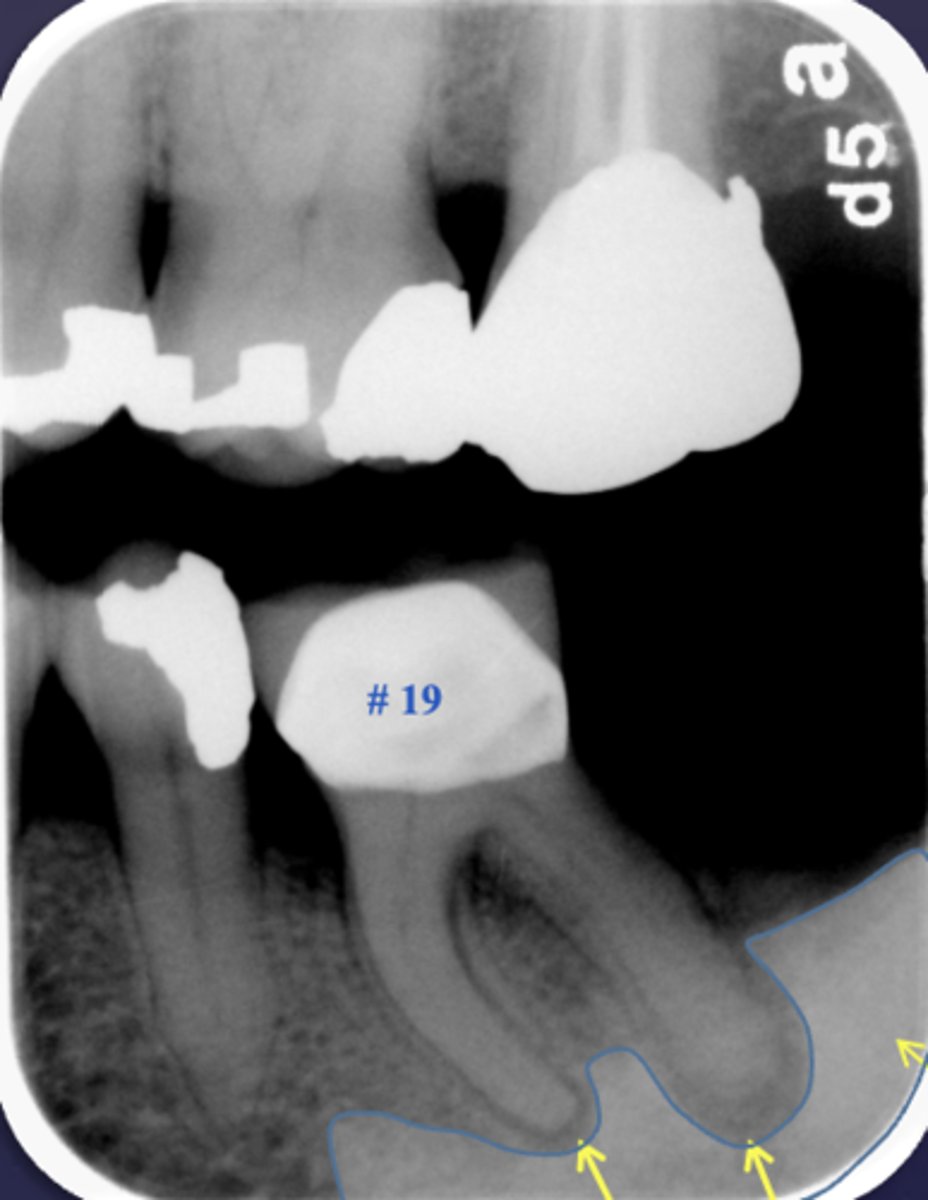

Periapical inflammatory disease can be located where?

- Apical to root apex

- Adjacent to accessory canal/root fracture/perforation

If a periapical lesion enlarges, the epicenter moves where?

away from root apex

What condition is present in this radiograph?

apical rarefying osteitis